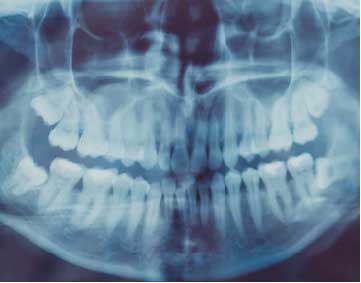

Oral surgery

Surgical specialty that includes diagnosis, surgery and related treatments of a wide spectrum of diseases, wounds and aesthetic aspects of the mouth, teeth, face, head and neck.